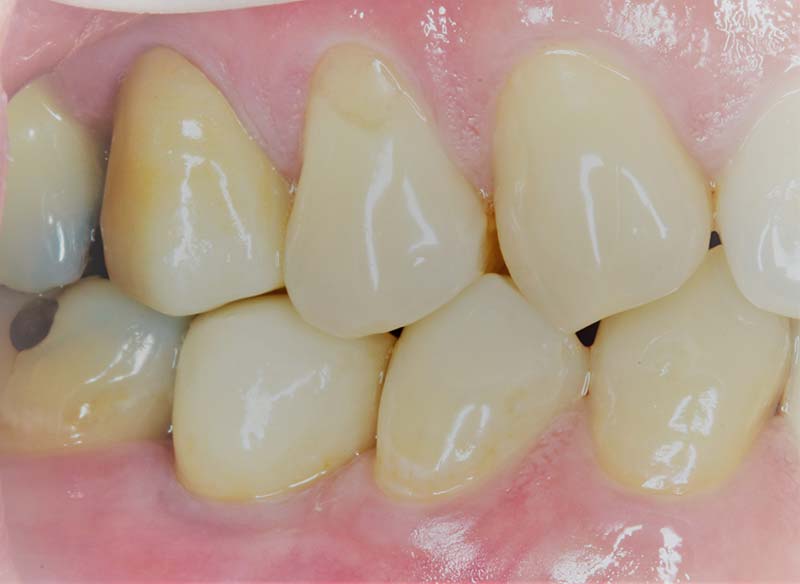

- 植牙平均受力比傳統假牙好,提供更好的支撐,外觀與咬合力量更接近真牙。

- 裝上假牙—假牙製作完成後,利用螺絲或黏合方式固定假牙,並調整咬合。